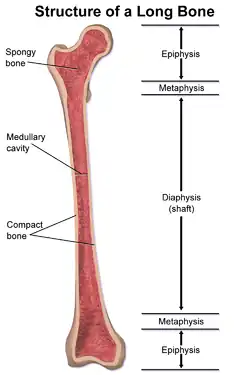

A fratura femoral é uma fratura óssea na parte superior da perna que afeta o osso mais longo e

Podem ser divididas em fracturas proximais (fratura do quadril), fraturas mediais (da diáfise do fêmur) e as fracturas distais (fratura do joelho).

Para fraturas da diáfise, a redução e haste intramedular são recomendados atualmente. O osso é realinhado, e em seguida uma haste de metal é fixada atravessando a medula óssea. A haste é estabilizada com pregos em cada extremidade. Este método oferece menos exposição, 98% de consolidação, menores taxas de infecção (1%-2%) e menos cicatrizes.[13]